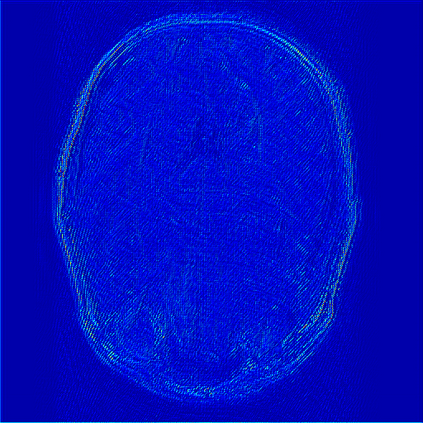

Reconstructing magnetic resonance (MR) images from undersampled data is a challenging problem due to various artifacts introduced by the under-sampling operation. Recent deep learning-based methods for MR image reconstruction usually leverage a generic auto-encoder architecture which captures low-level features at the initial layers and high?level features at the deeper layers. Such networks focus much on global features which may not be optimal to reconstruct the fully-sampled image. In this paper, we propose an Over-and-Under Complete Convolu?tional Recurrent Neural Network (OUCR), which consists of an overcomplete and an undercomplete Convolutional Recurrent Neural Network(CRNN). The overcomplete branch gives special attention in learning local structures by restraining the receptive field of the network. Combining it with the undercomplete branch leads to a network which focuses more on low-level features without losing out on the global structures. Extensive experiments on two datasets demonstrate that the proposed method achieves significant improvements over the compressed sensing and popular deep learning-based methods with less number of trainable parameters. Our code is available at https://github.com/guopengf/OUCR.